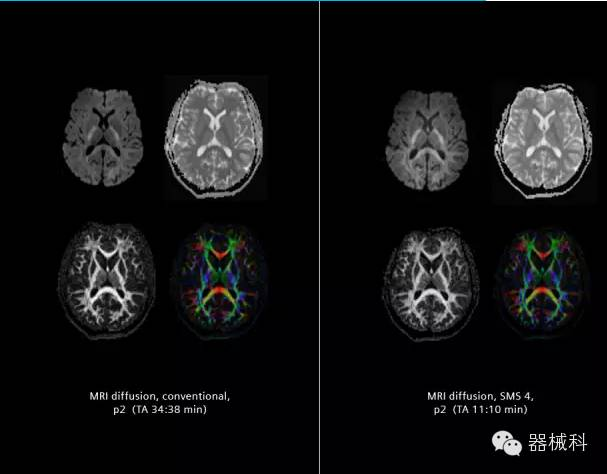

在2015年RSNA上,西門子隆重發(fā)布了Simultaneous Multi-slices 技術(shù)(即同時(shí)多層采集技術(shù),簡(jiǎn)稱SMS),這是磁共振掃描技術(shù)中第一次引入“同時(shí)多層”的概念,此概念技術(shù)的發(fā)布,將對(duì)未來磁共振成像領(lǐng)域帶來巨大的變革!

· 2012年,麻省總醫(yī)院Kawin Setsompop等在西門子7T 磁共振上獲得了使用SMS技術(shù)的得到的同時(shí)多層diffusion和fMRI圖像,并得出結(jié)論,采用全新的SMS技術(shù),可以大幅度提高空間分辨率和采集速度。

SMS技術(shù)可以將原本用于科研的高級(jí)成像技術(shù)轉(zhuǎn)化成臨床常規(guī)。

SMS可以有效提升高級(jí)功能成像精準(zhǔn)度。

擁有了SMS“同時(shí)多層”采集技術(shù)之后,用戶可以在非常短的時(shí)間內(nèi)完成MR掃描,結(jié)合西門子靜音技術(shù),大大提高患者的舒適性,或在單位時(shí)間內(nèi)采集更多的數(shù)據(jù),也可以得到高精度、高準(zhǔn)確性、大數(shù)量的功能成像數(shù)據(jù),為臨床和科研提供強(qiáng)大的支持。專家認(rèn)為,SMS“同時(shí)多層”采集技術(shù)未來在 提高成像質(zhì)量、外科手術(shù)計(jì)劃、降低術(shù)后神經(jīng)功能缺陷、提高fMRI的時(shí)間采集效率、提高靜息態(tài)功能磁共振數(shù)據(jù)質(zhì)量等方面將帶來深遠(yuǎn)影響,希望該技術(shù)可以盡早面世,引領(lǐng)磁共振進(jìn)入多層時(shí)代!